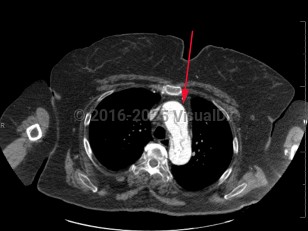

Aortic dissectionAortic dissection